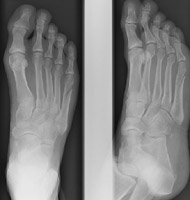

- Click on the image for a larger versionBOblique radiograph of the foot. Two years later the patient returns for continued pain. A radiograph reveals nonunion of the fracture, a frequent complication of the Jones fracture.